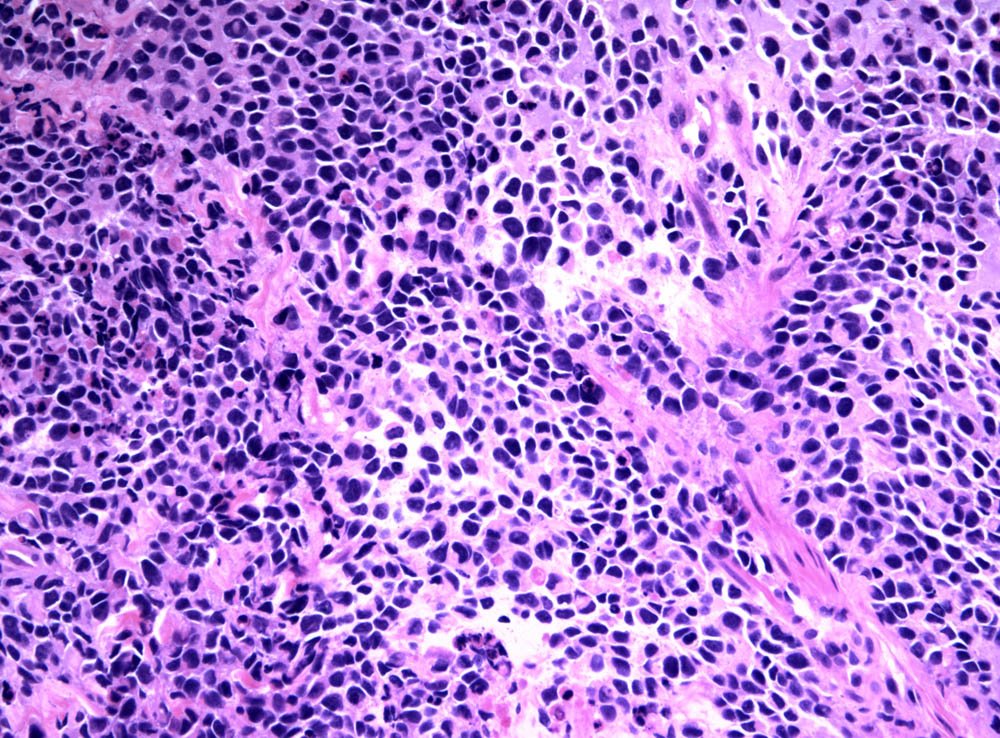

Case: ProstateMass

Specials to Order:

Final Diagnosis: